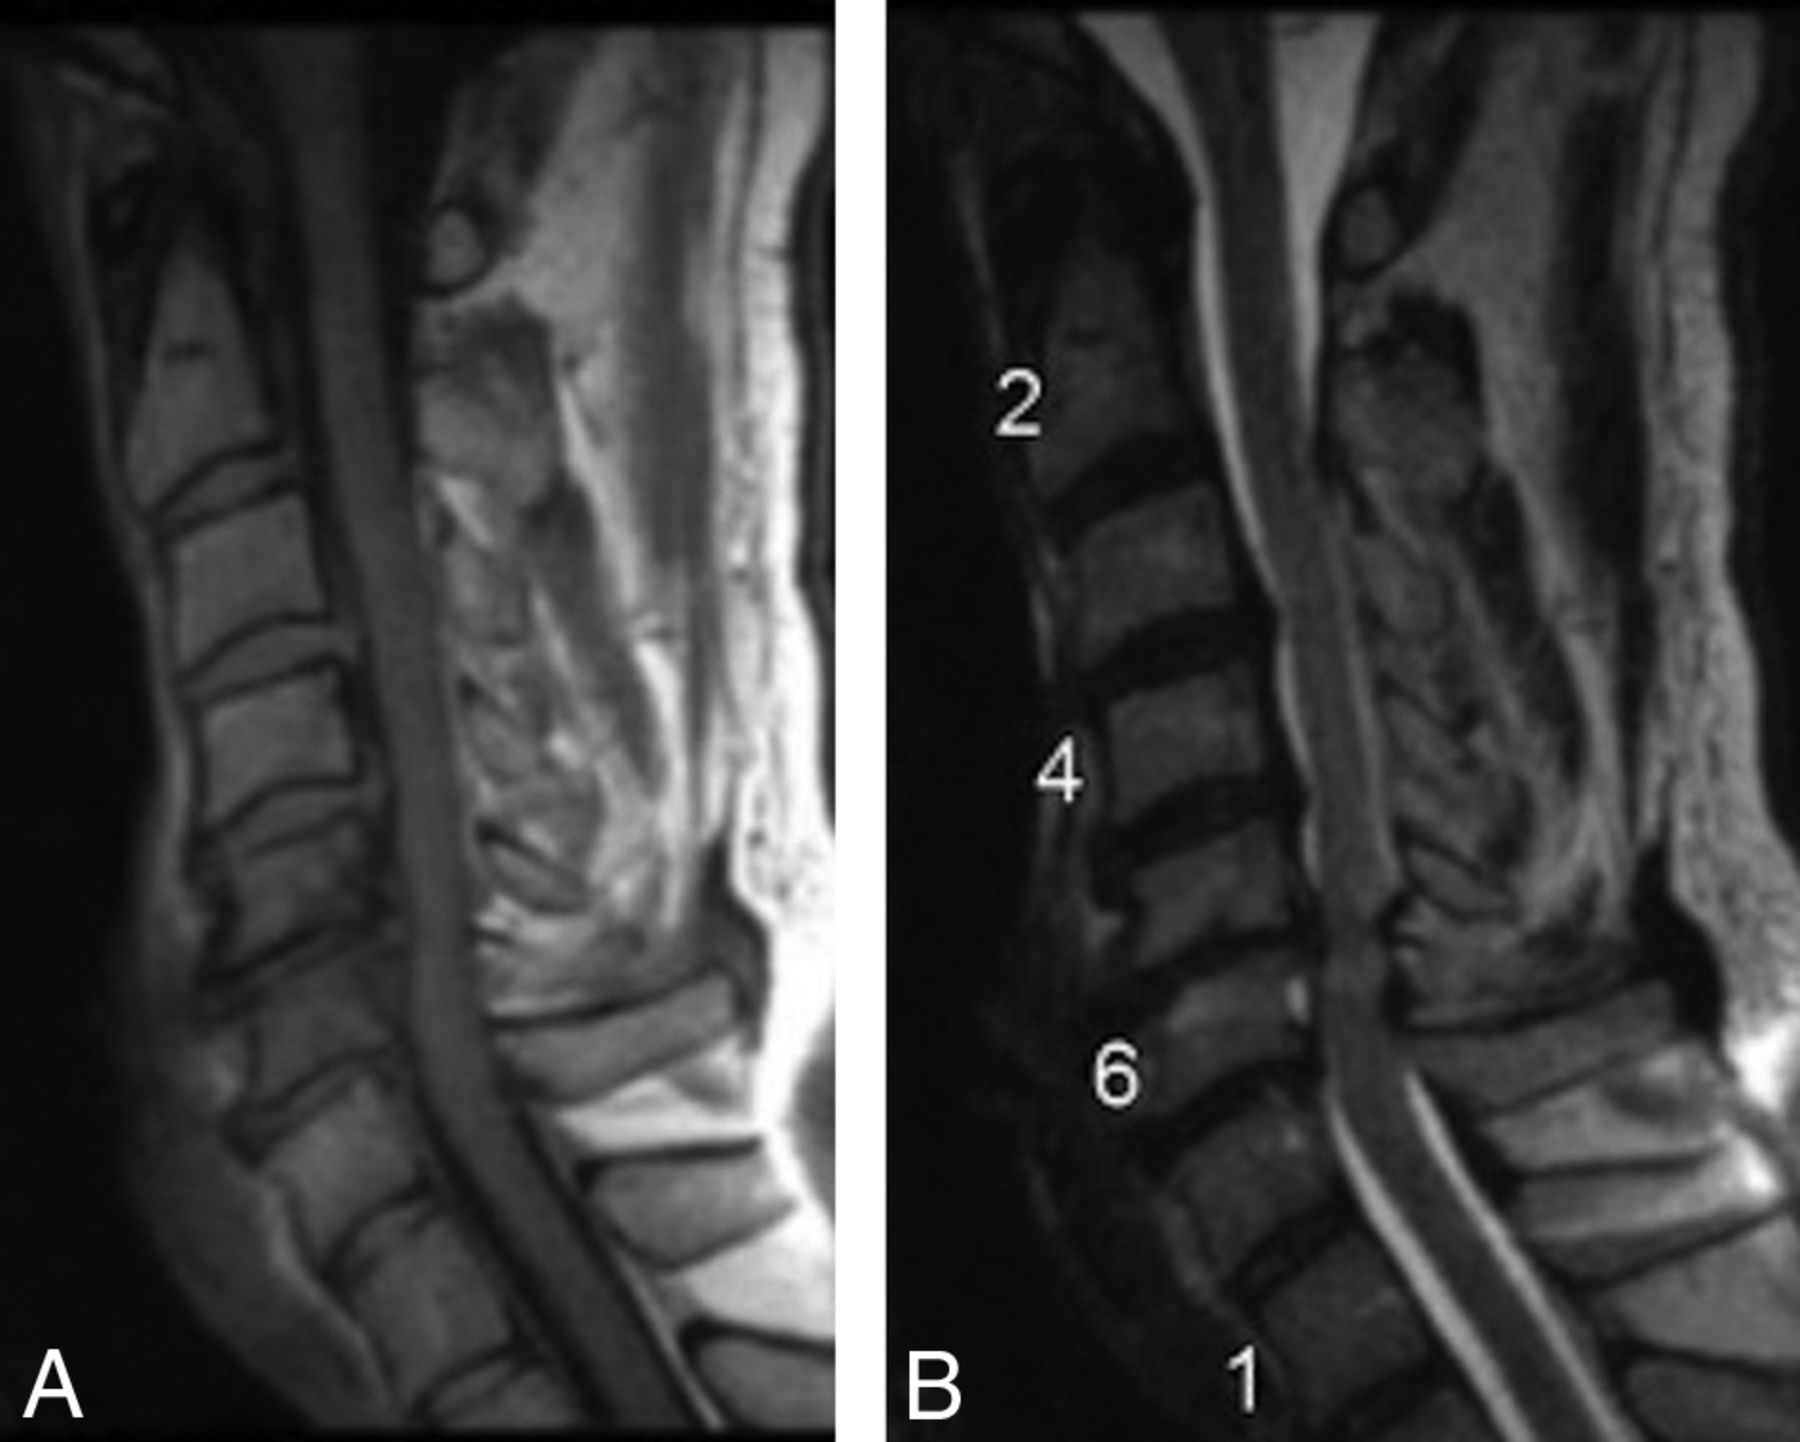

A 49-year-old male patient who underwent anterior fusion at C5–C6 and C6–C7 and was biopsy-positive for P acnes at both levels. Preoperative sagittal MR imaging (T1- and T2-weighted) shows disc bulges at C5–C6 and C6–C7 with no evidence of MC1.